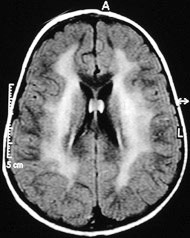

对化疗后出现严重认知障碍的癌症病人进行的大脑核磁共振成像扫描结果。

一项新的动物试验表明,3种广泛使用的化疗药物能够对健康脑细胞造成永久损伤。这项研究将有助于解释一系列统称为“化学脑”的认知问题——大约80%的癌症患者都会出现记忆力下降与紊乱以及无法集中精神等问题。并未参与此项工作的美国纽约州布法罗大学医学院儿科肿瘤学家Patricia Duffner指出:“这一发现为研究我们长期关注的问题提供了生理学基础。”